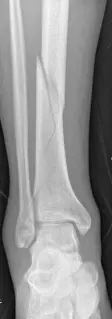

2. الأشعة السينية (X-rays): تُظهر صور الأشعة السينية التقليدية الكسر وموقعه ومدى انزياحه. يتم أخذ عدة لقطات من زوايا مختلفة.

توضيح طبي: صور أشعة سينية توضح كسر قصبة الساق والبلافون